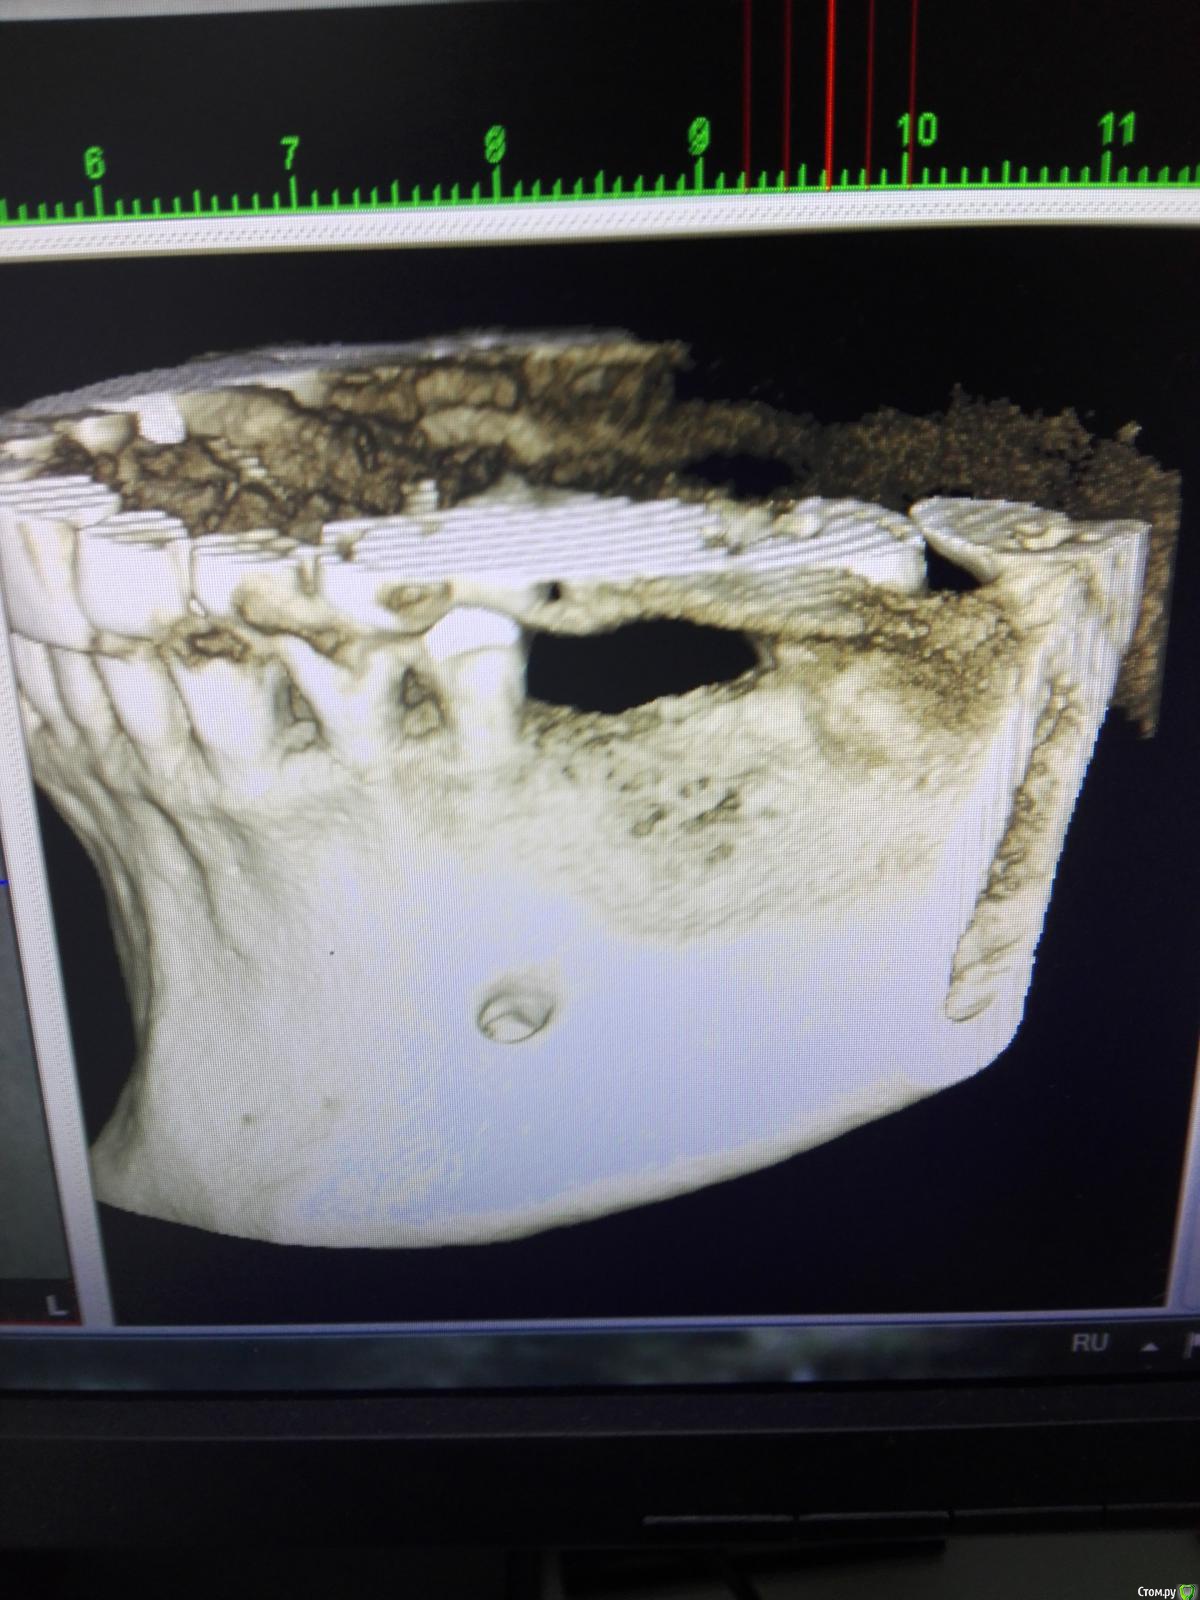

ДЖЕК Опубликовано 5 февраля, 2011 Поделиться Опубликовано 5 февраля, 2011 Думаю, мы говорим о канале Робинсона.Сосудисто-нервный пучек , непостоянный.Заходит выше нижнечелюстного отверстия , выходит там , где говорите. Часто этот стервец ответственен , что анестезия в этой области не получается с первого удара. Ссылка на комментарий

Aldo Rain Опубликовано 5 февраля, 2011 Поделиться Опубликовано 5 февраля, 2011 Будет возможность покажите срез с КТ Ссылка на комментарий

talshik Опубликовано 6 февраля, 2011 Поделиться Опубликовано 6 февраля, 2011 В литературе Анатомия дентальной имплантации можно его увидеть на картинке и на КТ.Купил и любуюсь многим чем. Ссылка на комментарий

ДЖЕК Опубликовано 11 февраля, 2011 Поделиться Опубликовано 11 февраля, 2011 ПЕРЕДНИЙ ВЕРХНИЙ АЛЬВЕОЛЯРНЫЙ СОСУДИСТО-НЕРВНЫЙ ПУЧЕК. Ж.ГОДИ.АТЛАС ДЕНТАЛЬНОЙ ИМПЛАНТАЦИИ Ссылка на комментарий

karasov Опубликовано 20 октября, 2016 Поделиться Опубликовано 20 октября, 2016 (изменено) В области 36 работал с ламиной. Наткнулся на нерв. Причем два. Один обошел , второй нет. Что ждать?на кт ееееле заметны Изменено 20 октября, 2016 пользователем karasov Ссылка на комментарий

karasov Опубликовано 21 октября, 2016 Поделиться Опубликовано 21 октября, 2016 не похож на нерв. имхо.По кт есть однозначно связь с нижним альвеолярным. Визуально на сосуд не похоже Ссылка на комментарий